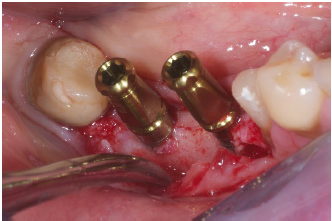

sutures. 8 Months after surgery one can notice the new aspect of the ridge (Figure 7) and after flaps were opened to exposed the new ridge one can notice that the

new horizontal volume coud than receive 4.2mm diameter implants

(Resista, Omegna, Italy) without any problem (Figure 8). The next

picture (Figure 9) shows how the two fixtures were properly

adjusted to the new anatomy. Three monts later the implants were

Figure 8:Insertion of two 4.2mm fixtures.

Figure 9: implants in place.